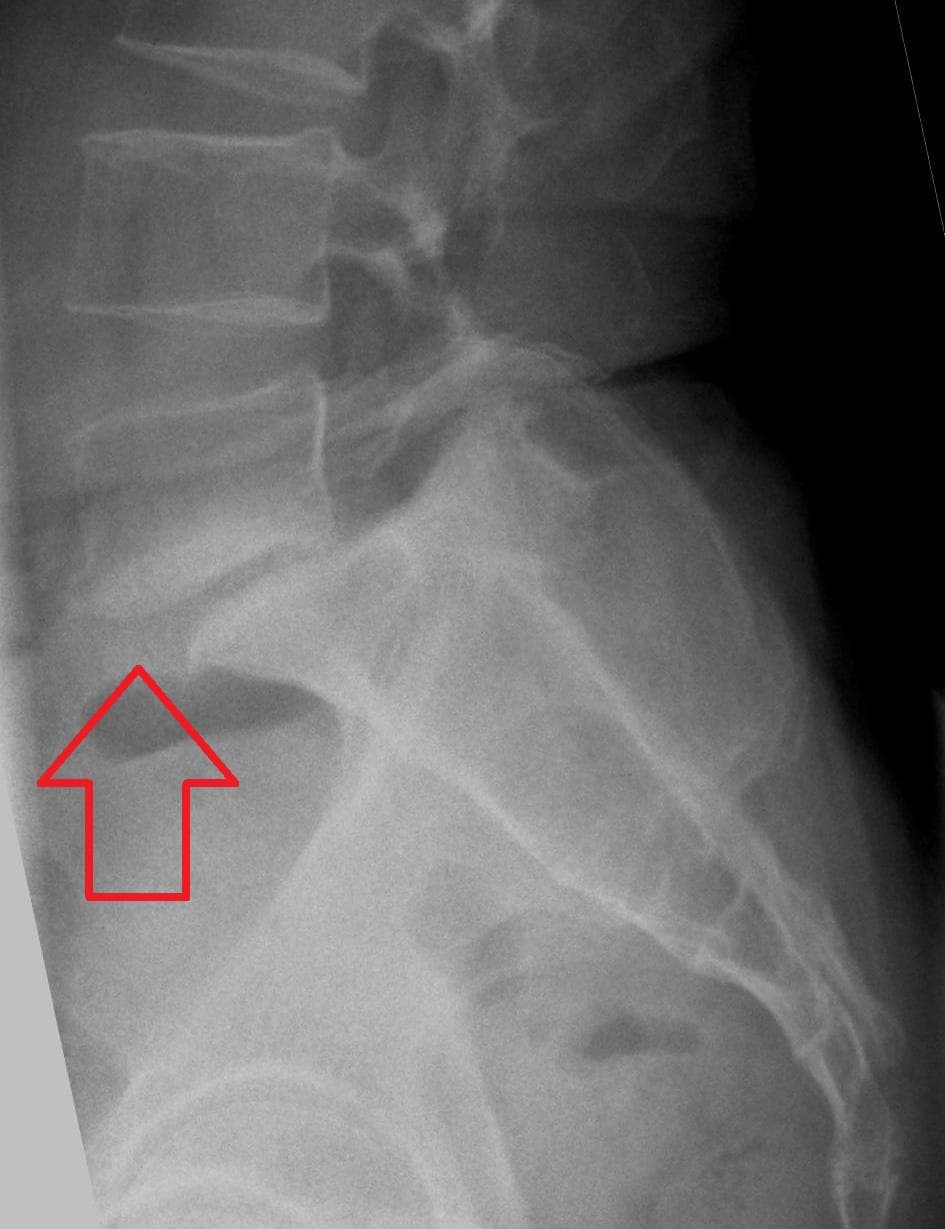

Le spondylolisthésis (du grec ancien , vertèbre, et , action de glisser) désigne une affection du squelette humain, caractérisée par le glissement d'une vertèbre en avant de la vertèbre située en dessous d'elle (antéspondylolisthésis) ou en arrière (rétrolisthésis). Les vertèbres les plus souvent concernées sont la quatrième et la cinquième vertèbre lombaire. La spondylolyse est une perte de continuité de l'isthme articulaire (pars interarticularis), situé entre les deux apophyses articulaires supérieure et inférieure de l'arc vertébral postérieur. Elle survient le plus souvent au niveau d'un étage vertébral lombaire bas, habituellement le dernier étage mobile. Elle peut être unilatérale ou bilatérale, induisant alors une micro mobilité ou une mobilité de l'arc postérieur. Elle peut être aiguë, traumatique, correspondant à un trait de fracture vrai, ou chronique, sans notion de vrai traumatisme. La perte de continuité s'organise alors sous la forme d'un tissu fibreux ou plus rarement pseudo-kystique plus ou moins hypertrophique dit « nodule de Gill », qui peut être agressif pour les racines nerveuses au contact. La lyse peut survenir dans l’enfance, mais aussi à l’âge adulte. La fréquence de la spondylolyse au niveau lombaire est remarquablement élevée : de l'ordre de 3 à 7 % dans la population générale, beaucoup plus dans certains groupes. Si Inuits et Bushmen sont classiquement des groupes à risque, la fréquence des spondylolyses est de 14 % chez les athlètes de haut niveau, particulièrement 20 % chez les danseurs, et de 11 à 17 % chez les gymnastes et les rameurs, au point que la constatation d'une spondylolyse puisse être considérée comme presque physiologique dans certains groupes de sportifs... Le spondylolisthésis est un déplacement permanent du corps vertébral en avant sur le corps vertébral sous-jacent, constituant un antéspondylolisthésis, ou en arrière (rétrolisthésis). Il est deux à trois fois moins fréquent que la spondylolyse isthmique.